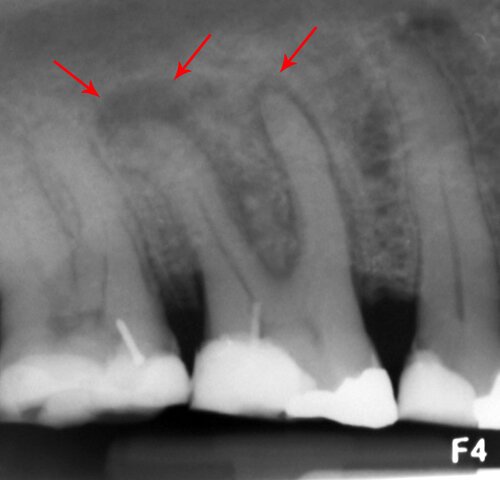

- Bác sĩ sẽ tiến hành thăm khám, chụp X – Quang để xác định chiều dài, hình dạng, vị trí và tình trạng xương xung quanh vị trí răng cần nhổ. Từ đó, bác sĩ ước tính mức độ khó của ca tiểu phẫu và hướng nhổ răng hợp lý nhất.

Chẩn đoán ổ nhiễm trùng chân răng trên phim X-quang cận chóp